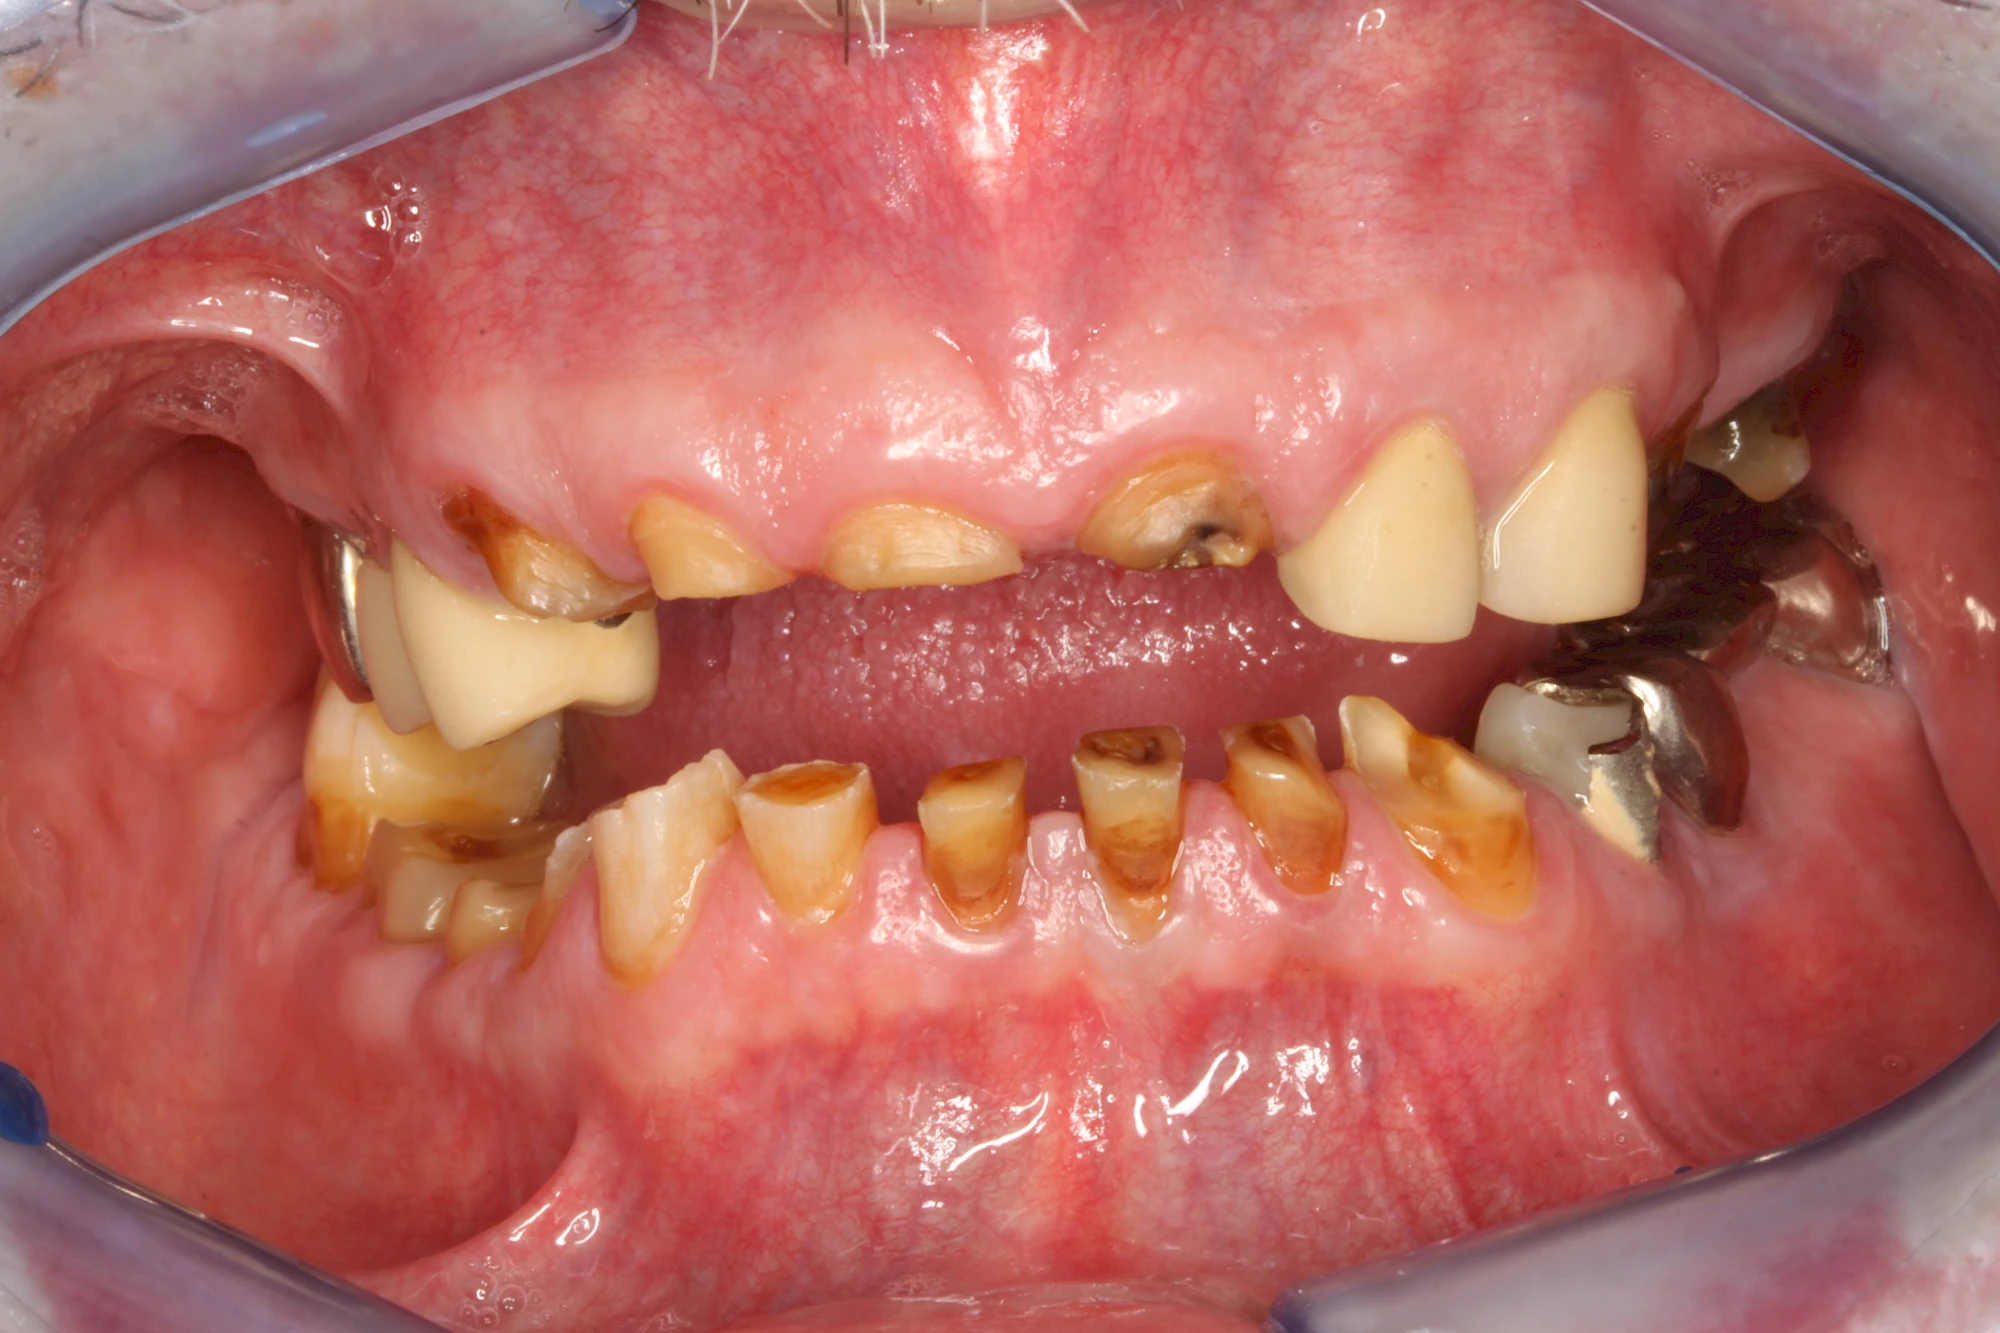

Auswaschung (Erosion) dagegen ist eine Verschleißerscheinung der Zähne aufgrund von immer wiederkehrenden Säureangriffen durch die Nahrung, verstärkt zum Beispiel durch den Genuss säurehaltiger Getränke oder Speisen. Auch bei Menschen mit einer Essstörung (z. B. Bulimie) können die Zähne durch die Magensäure ausgewaschen erscheinen.

Eine Sonderform sind sogenannte keilförmige Defekte im Bereich der Zahnhälse. Hier geht man davon aus, dass Knirschen und Pressen in Kombination mit falschen Putzgewohnheiten (zu hoher Putzdruck, Verwendung von Zahnpasta mit hohen Abrasionswerten) eine Rolle spielen.